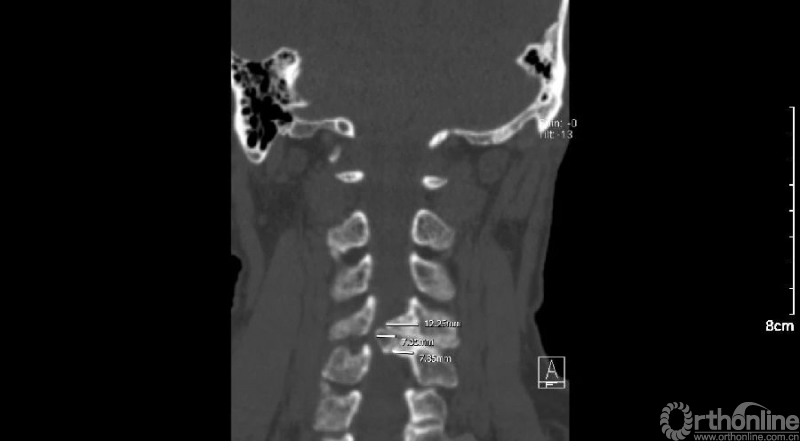

入院查体患者四肢肌张力高,双侧hoffman阳性。CT及MRI检查提示C4/5左侧关节突内缘有一巨大骨块(15mm*16mm),相应节段椎管严重狭窄。椎管内骨块的前端还有一游离骨块。

影像学资料